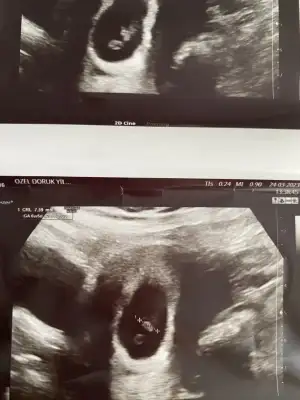

Karından ultrason bu arada

1679661590570.webp

plesantası sağda bu yüzden kız aşkım :D

Bu bebişler neden hep ortada durur anlamadım azıcım plesentaya yakın dursalar olmuyor sanki 😂😂😂 kız gibi kuzum saglıkla gelsin inşallah başka var mı foto

Birde şöyle var tek olan diğer foto bide ikisini attım